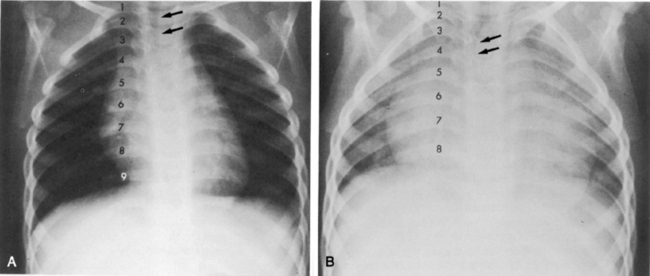

If the film is obtained during expiration, the heart will appear larger and less well defined. The lung fields will appear to be hazier and the pulmonary vascular markings more prominent. Hypoinflation of the lung fields can lead to misinterpretation of the images and misdiagnosis of a basilar pneumonia or cardiomegaly. Furthermore, if maximal inspiration is not present, the lungs can appear more congested and the trachea will appear to buckle to the right.21,24 Figure 10-2 illustrates these differences with two views obtained from a normal child during inspiration and expiration.

image

Fig. 10-2 Inspiratory and expiratory chest radiograph. Normal chest films obtained from the same child during inspiration and expiration. A, Inspiratory phase. Nine ribs can be counted above the diaphragm, indicating good inspiration. Alignment is good (note similarity of clavicles). Penetration of film is good (all vertebral bodies are visible; some pulmonary vascular markings can be seen). Intercostal spaces are equal; both sides of the diaphragm are visible. The mediastinum and trachea are straight (arrows). Heart borders are sharply defined, and heart size is normal. Pulmonary vascular markings are visible in the proximal two thirds of lung fields (normal). B, Expiratory phase. Only eight ribs are visible above the diaphragm (see numbers on ribs), indicating inadequate lung expansion. Alignment is good. Penetration of film is good. Intercostal spaces are narrow because expiration is occurring. Both sides of the diaphragm are hazy, and the left hemidiaphragm is not readily identifiable. The mediastinum appears widened, and the trachea seems to buckle to the right (arrows). Heart appears much larger than in A, and the heart borders are obliterated, but this is caused by expiration and reduction in apparent lung volume. Silhouette sign appears to be present, cardiothoracic size calculated from this view would be large, and pulmonary vascular markings appear prominent, but these are all artifacts caused by expiration.

(Courtesy H. Rex Gardner, Rush Presbyterian Saint Luke’s Hospital, Chicago, IL.)